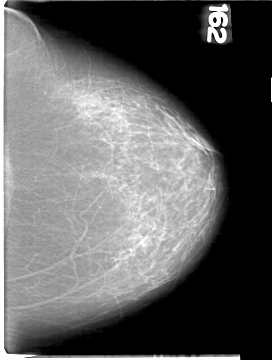

D_4094_1.RIGHT_CC

LEFT_CC LINES 5386 PIXELS_PER_LINE 4066 BITS_PER_PIXEL 12 RESOLUTION 43.5 NON_OVERLAY